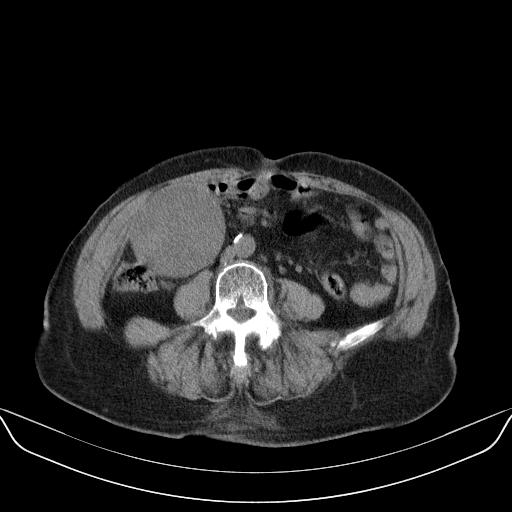

以下是引用yuhongjun在2010-3-12 6:32:00的发言:[br]回肠末端间质瘤,不除外阑尾粘液囊腺瘤,臀部注射性肉芽肿钙化. [br] [br]